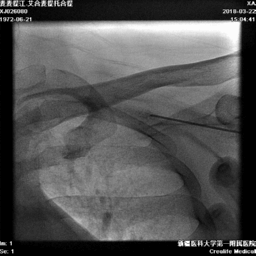

腋静脉穿刺

● 考虑CRTD植入电极数量较多,选择腋静脉穿刺避免远期并发症。

腋静脉穿刺技巧

● 穿刺困难时,可行造影,影像下穿刺

冠状窦寻找

● 使用强生十极寻找冠状窦后,顺势推送长鞘进入冠状窦内

冠状静脉造影

● 冠状静脉造影,选择靶血管侧静脉。血管远端无法看清,使用鞘中鞘造影靶血管

鞘中鞘超选靶血管造影

● 根据造影结果尝试选择侧静脉